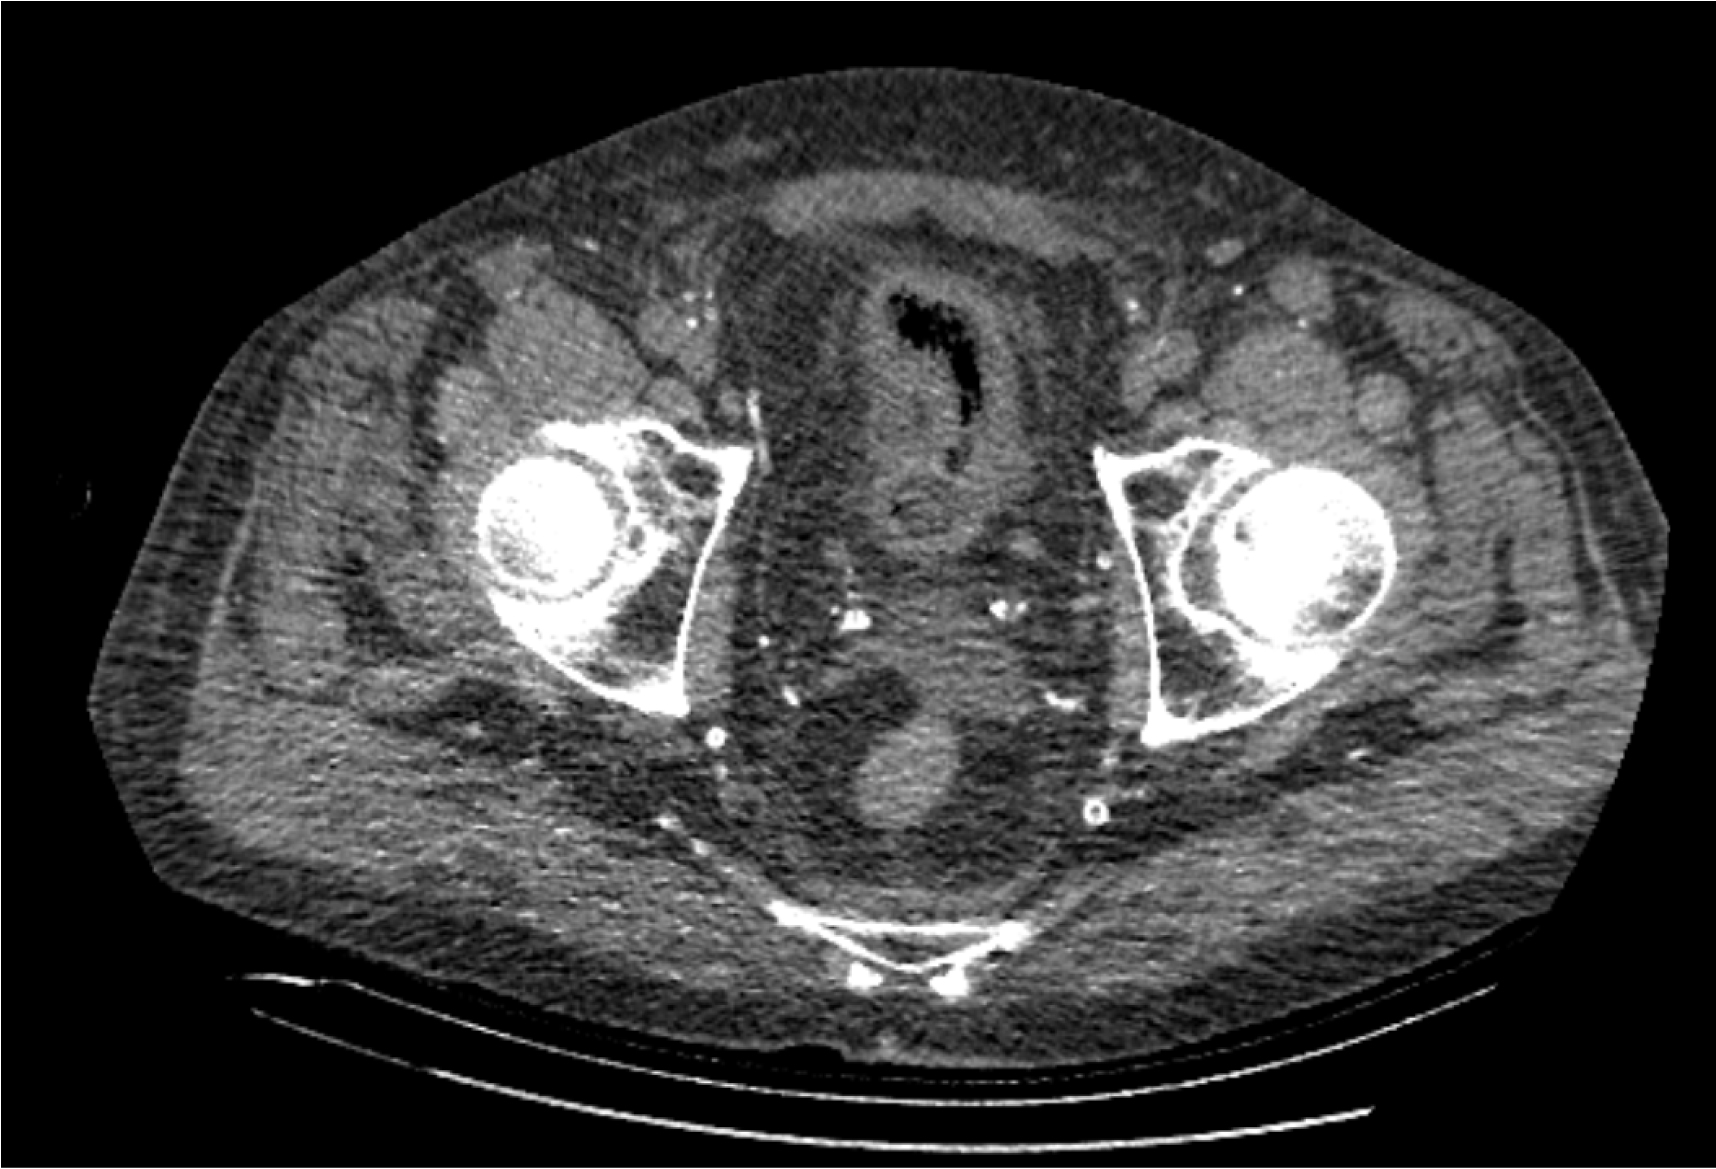

На следующий день состояние пациента оставалось тяжелым, с отрицательной динамикой, креатинин сыворотки возрос до 735,2 ммоль/л, Появились жалобы на слабость, тошноту. При осмотре: живот мягкий, вздут по всем отделам, при пальпации болезненный. Область почек не изменена, при пальпации безболезненна, патологических изменений в области почек не выявлено. Симптом поколачивания отрицательный билатерально. При УЗИ были обнаружены плевральный выпот по 300–400 мл с каждой стороны, гепатомегалия, увеличение размеров селезенки, асцит. Кроме того, в обеих почках были визуализированы тени, характерные для конкрементов. По данным компьютерной томографии (КТ) конкрементов не обнаружено, но в лоханке, на всем протяжении левого мочеточника и, частично, в правом мочеточнике, а также в мочевом пузыре визуализировался газ (рис. 1–6).

Рис. 4. Компьютерная томография органов брюшной полости, забрюшинного пространства, органов малого таза. Газ в почках

Рис. 5. Компьютерная томография органов брюшной полости, забрюшинного пространства, органов малого таза. Газ в левой почке

Рис. 6. Компьютерная томография органов брюшной полости, забрюшинного пространства, органов малого таза. Газ в верхнем полюсе левой почки